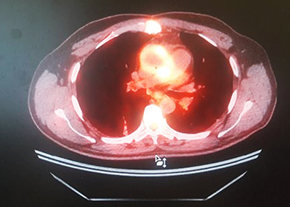

ПЭТ с 18F-ФДГ: ПЭТ/КТ-картина в пользу протезного эндокардита аортального клапана.